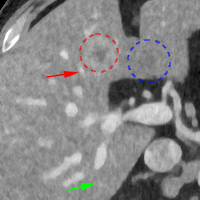

To show the denoising effect of the selected networks, we took two representative slices as shown in Figs. 5 and 7. And Figs. 6 and 8 are the zoomed regions-of-interest (ROIs) marked by the red rectangles in Figs. 5 and 7. All the networks demonstrated certain denoising capabilities. However, CNN-MSE blurred the images and introduced waxy artifacts as expected, which are easily observed in the zoomed ROIs in Figs. 6e and 8e. WGAN-MSE was able to improve the result of CNN-MSE by avoiding over-smooth but minor streak artifacts can still be observed especially compared to CNN-VGG and WGAN-VGG. Meanwhile, using WGAN or GAN alone generated stronger noise (Figs. 6g and 8g) than the other networks enhanced a few white structures in the WGAN/GAN generated images, which are originated from the low dose streak artifact in LDCT images, while on the contrary the CNN-VGG and WGAN-VGG images are visually more similar to the NDCT images. This is because the VGG loss used in CNN-VGG and WGAN-VGG is computed in a feature space that is trained previously on a very large natural image dataset [48]. By using VGG loss, we transferred the knowledge of human perception that is embedded in VGG network to CT image quality evaluation. The performance of using WGAN or GAN alone is not acceptable because it only maps the data distribution from LDCT to NDCT but does not guarantee the image content correspondence. As for the lesion detection in these two slices, all the networks enhance the lesion visibility compared to the original noisy low dose FBP images as noise is reduced by the different approaches.

As for iterative reconstruction technique, the reconstruction results depend greatly on the choices of the regularization parameters. The implemented dictionary learning reconstruction (DictRecon) result gave the most aggressive noise reduction effect compared to the network outputs as a result of strong regularization. However, it over-smoothed some fine structures. For example, in Fig. 8, the vessel pointed by the green arrow was smeared out while it is easily identifiable in NDCT as well as WGAN-VGG images. Yet, as an iterative reconstruction method, DictRecon has its advantage over post-processing method. As pointed by the red arrow in Fig 8, there is a bright spot which can be seen in DictRecon and NDCT images, but is not observable in LDCT and network processed images. Since the WGAN-VGG image is generated from LDCT image, in which this bright spot is not easily observed, it is reasonable that we do not see the bright spot in the images processed by neural networks. In other words, we do not want the network to generate structure that does not exist in the original images. In short, the proposed WGAN-VGG network is a post-processing method and information that is lost during the FBP reconstruction cannot easily be recovered, which is one limitation for all the post-processing methods. On the other hand, as an iterative reconstruction method, DictRecon algorithm generates images from raw data, which has more information than the post-processing methods.